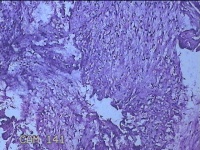

左大腿内侧包块

性别

男

年龄

21岁

临床诊断

脂肪瘤

一般病史

左大腿内侧起包块一月余。

标本名称

大体所见

灰白暗红色包块2.5x2x0.8cm一个,表面糜烂,切开包块呈实性,切面灰白暗红色,质软。

图1

图2